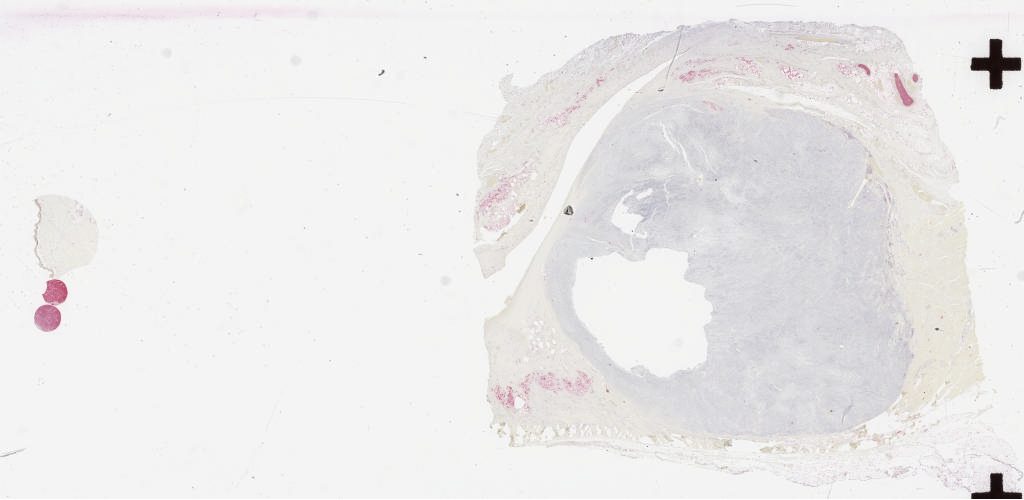

s100.svs

163344

x

79678

@

40X